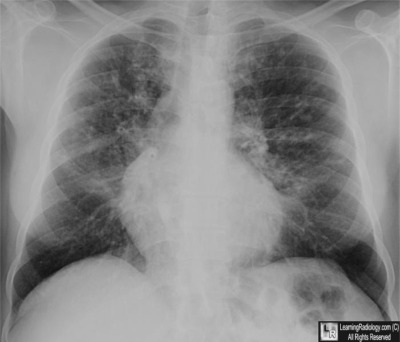

Case of the Week 549

What is the most likely diagnosis?

• 28 year-old with history of recurrent pulmonary infections and diabetes

Frontal Radiograph of Chest

5. Cystic Fibrosis

Cystic Fibrosis

General considerations

• Disease of abnormal exocrine gland function

• Autosomal recessive almost always in Caucasians

• Defect in gene which codes for cystic fibrosis transmembrane conductance regulator (CFTR)

• Major clinical manifestations are pulmonary and pancreatic insufficiency

• Elevated concentration of sodium and chloride in sweat

• Most patients are diagnosed by age 1year